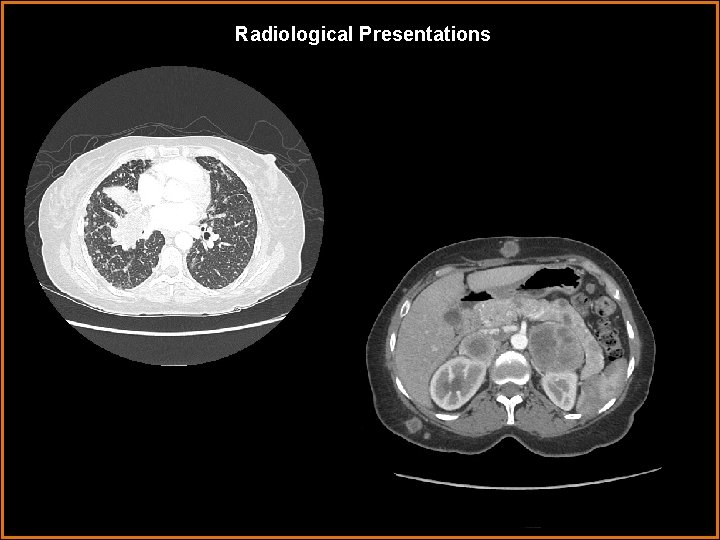

Findings and Differentials Findings: PA and lateral radiographs demonstrate innumerable small nodules in a miliary pattern. Also, increased opacity in the right base obscures the heart border with depression of the minor fissure. The lateral image confirms right middle lobe atelectasis. CT imaging through the lung bases confirms milary nodules in the lung and atelectasis of the right middle lobe. The abdominal image reveals bilateral adrenal masses and subcutaneous lesions. Differentials: • Metastases • Miliary infection